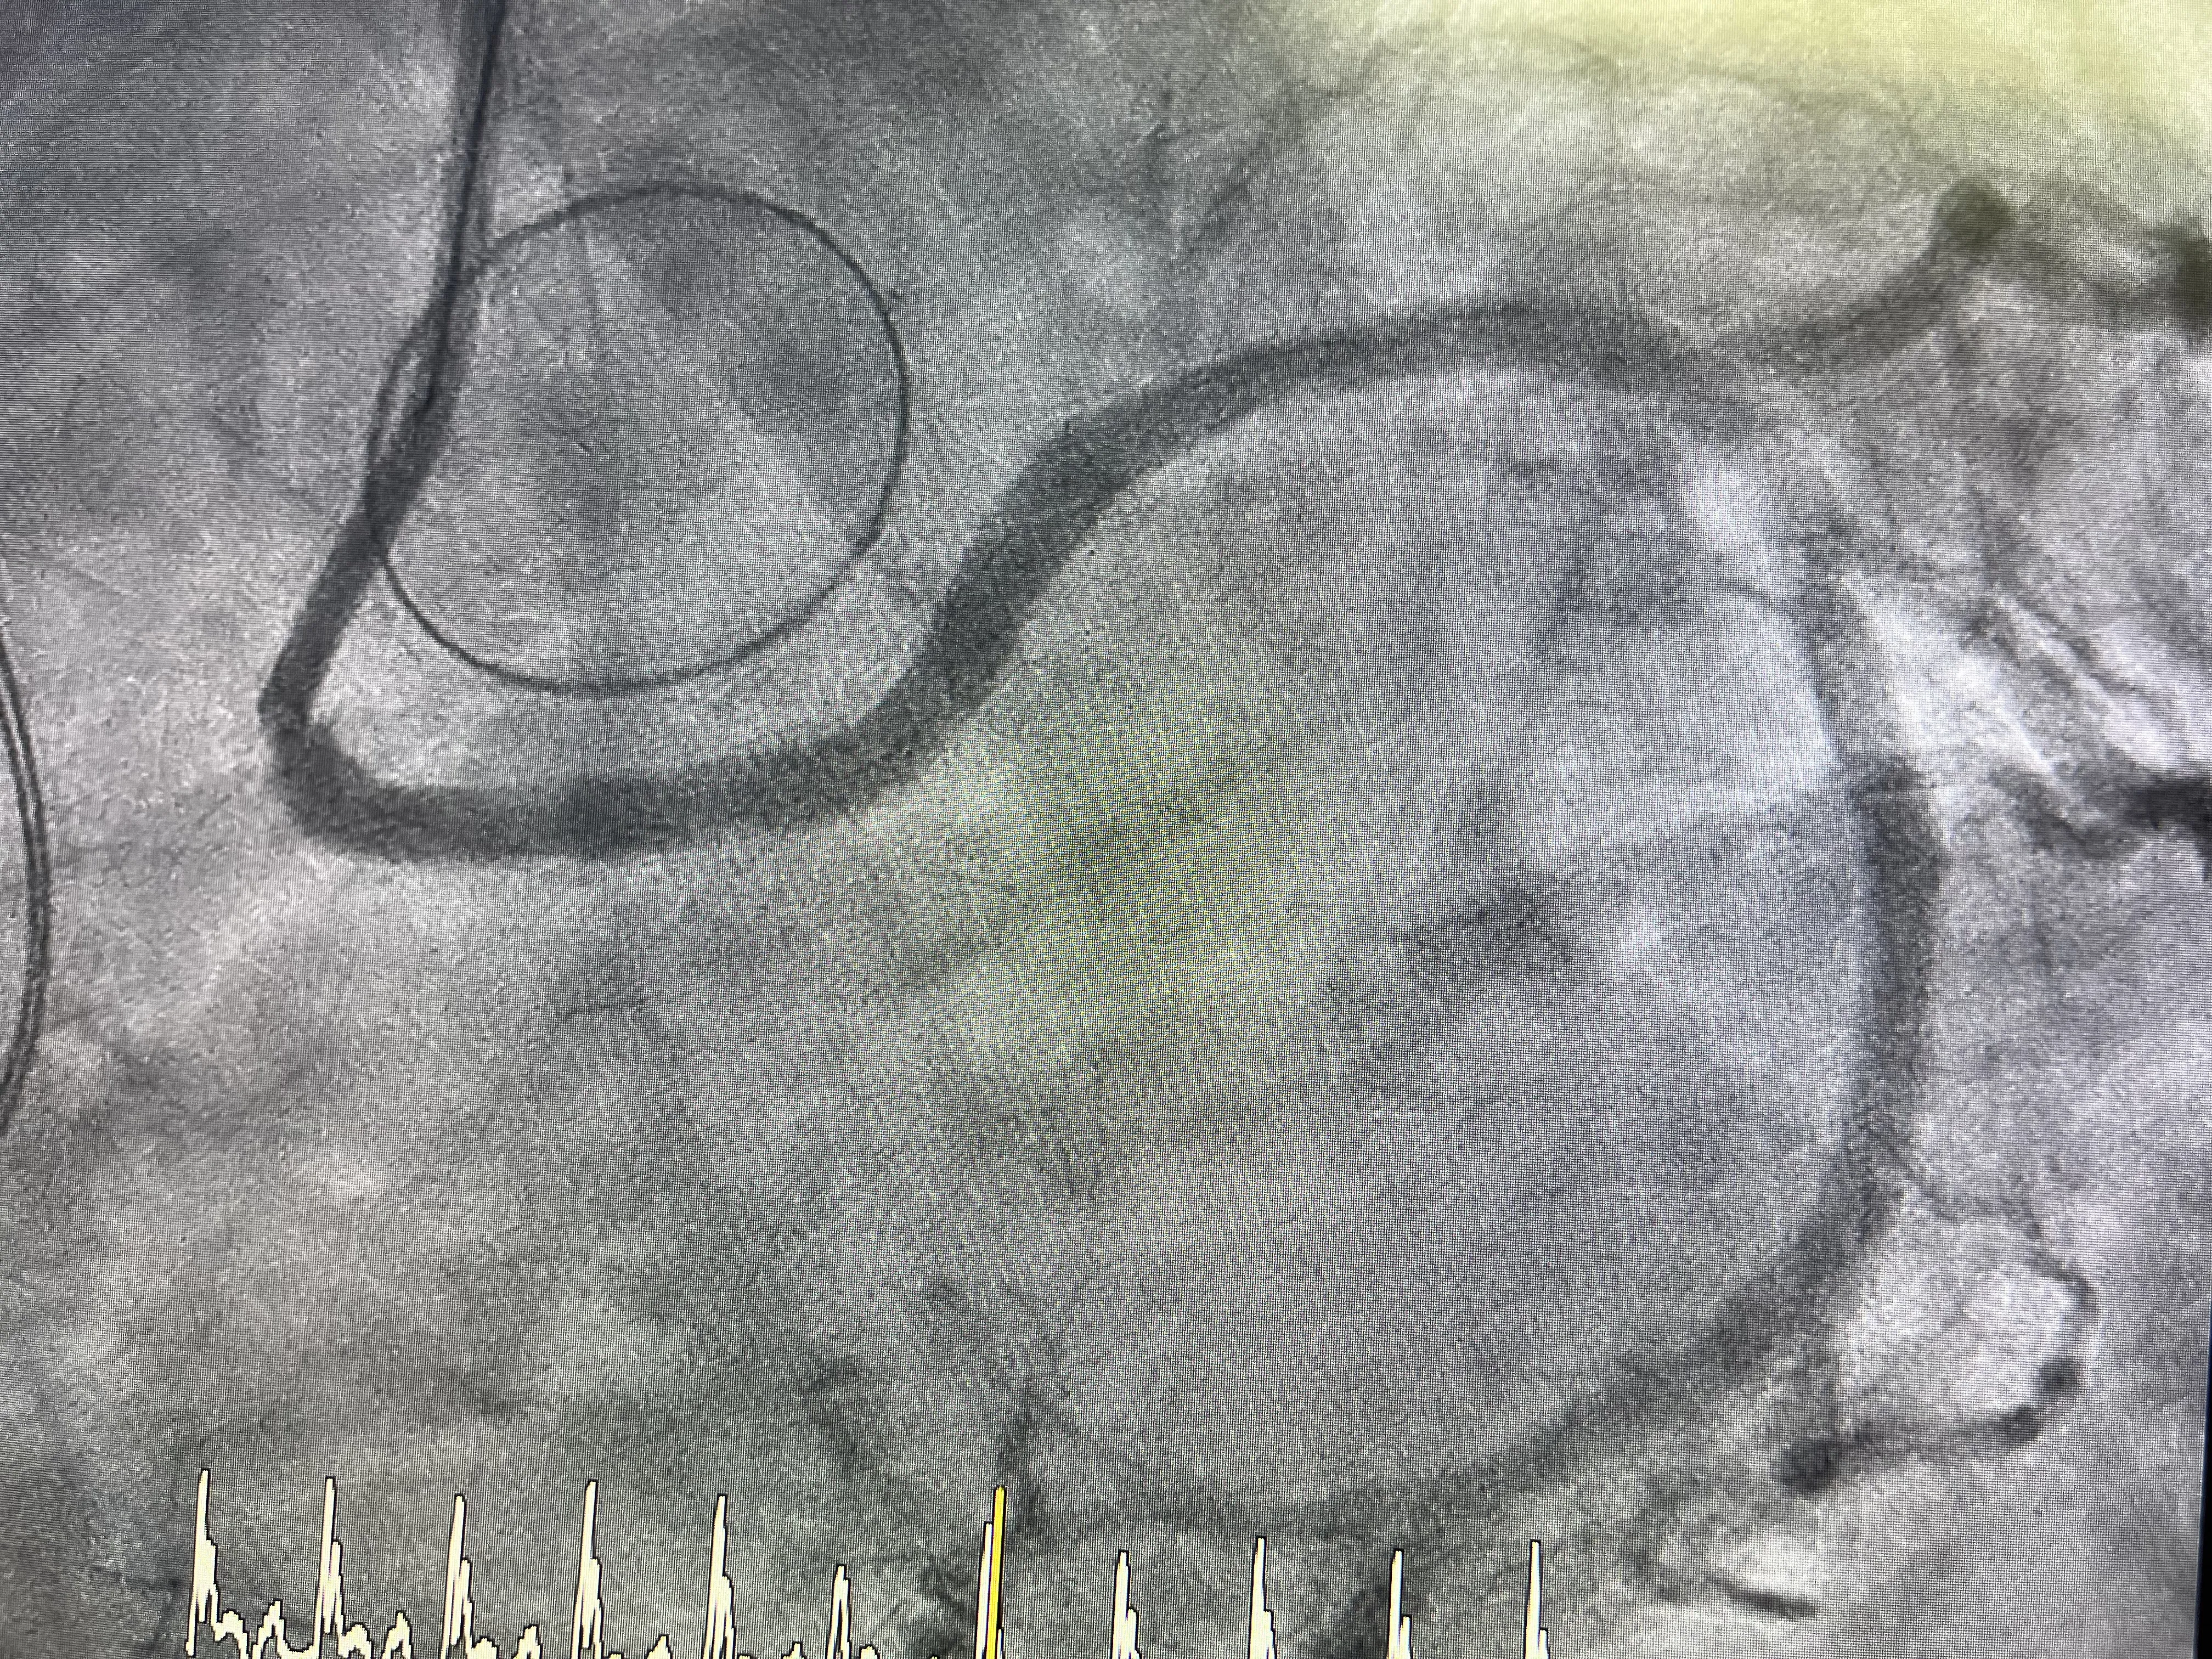

Durante el cateterismo, el objetivo principal es visualizar el árbol coronario y localizar la causa de la elevación del ST. Al inyectar contraste y analizar las imágenes, se hace evidente que la arteria circunfleja está ocluida. La sorpresa, aunque coherente con la anatomía conocida, es que la oclusión no se debe a una placa aterosclerótica inestable, sino a la propia sutura de la válvula mecánica. En otras palabras, la circunfleja ha sido literalmente suturada y estrangulada durante la fijación de la prótesis valvular.

Este hallazgo explica de forma directa el infarto en territorio inferior y la inestabilidad hemodinámica del paciente. El flujo coronario hacia la zona irrigada por la circunfleja está comprometido de forma crítica, generando isquemia severa. En ese momento, el reto del equipo de hemodinámica es doble: por un lado, confirmar que la causa es mecánica y, por otro, intentar restablecer el flujo a pesar de la presencia de la válvula mecánica. No se trata de una angioplastia convencional, sino de una situación límite condicionada por una complicación quirúrgica.

Aun así, se decide intentar la reapertura de la arteria circunfleja mediante técnicas percutáneas. El cateterismo se convierte entonces en la herramienta terapéutica central para revertir el daño. Este enfoque ilustra cómo, incluso tras una cirugía cardíaca mayor, la hemodinámica intervencionista puede ofrecer una salida a complicaciones graves. El caso real de estenosis circunfleja pasa así de ser un problema puramente quirúrgico a un escenario híbrido donde la colaboración entre cirujanos y hemodinamistas es esencial.